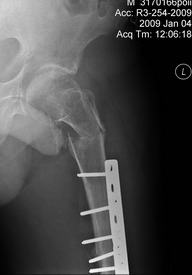

Р-гр шейки

Теперь ситуация более ясная. Оптимальным тут, очевидно, было бы малоинвазивное удаление пластины и закрытый интрамедуллярный остеосинтез длинной гаммой или другим проксимальным гвоздем. Это не только обеспечило бы надежную фиксацию всех проблемных отделов бедра, но и позволило бы немедленную полную нагрузку.

Другие варианты менее привлекательны, хотя в итоге могли бы привести к успеху. Но ценой большей травматичности, длительности лечения, неудобств, трудоемкости и с бОльшими рисками неприятностей. Вариантов очень много - скелетное вытяжение, тазобедренная повязка, остеосинтез DHS или другой пластиной с угловой стабильностью, остеосинтез таким или другим аппаратом...